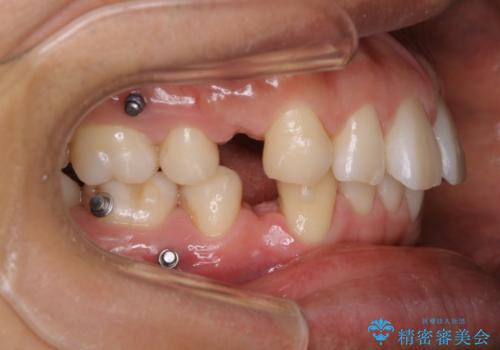

矯正中は汚れが付きやすいため、着色がとても多く付いていました。

抜歯したスペースや装置の周りの磨き方などとても難しため、定期的にクリーニングをおすすめします。